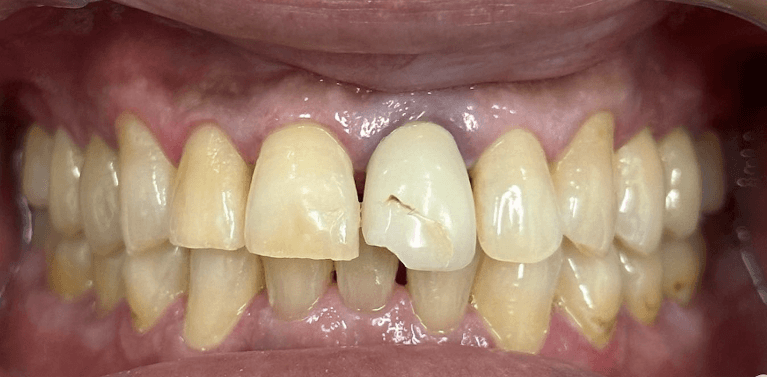

Broken Upper Central incisor with root canal replaced with Immediate implant after extraction.